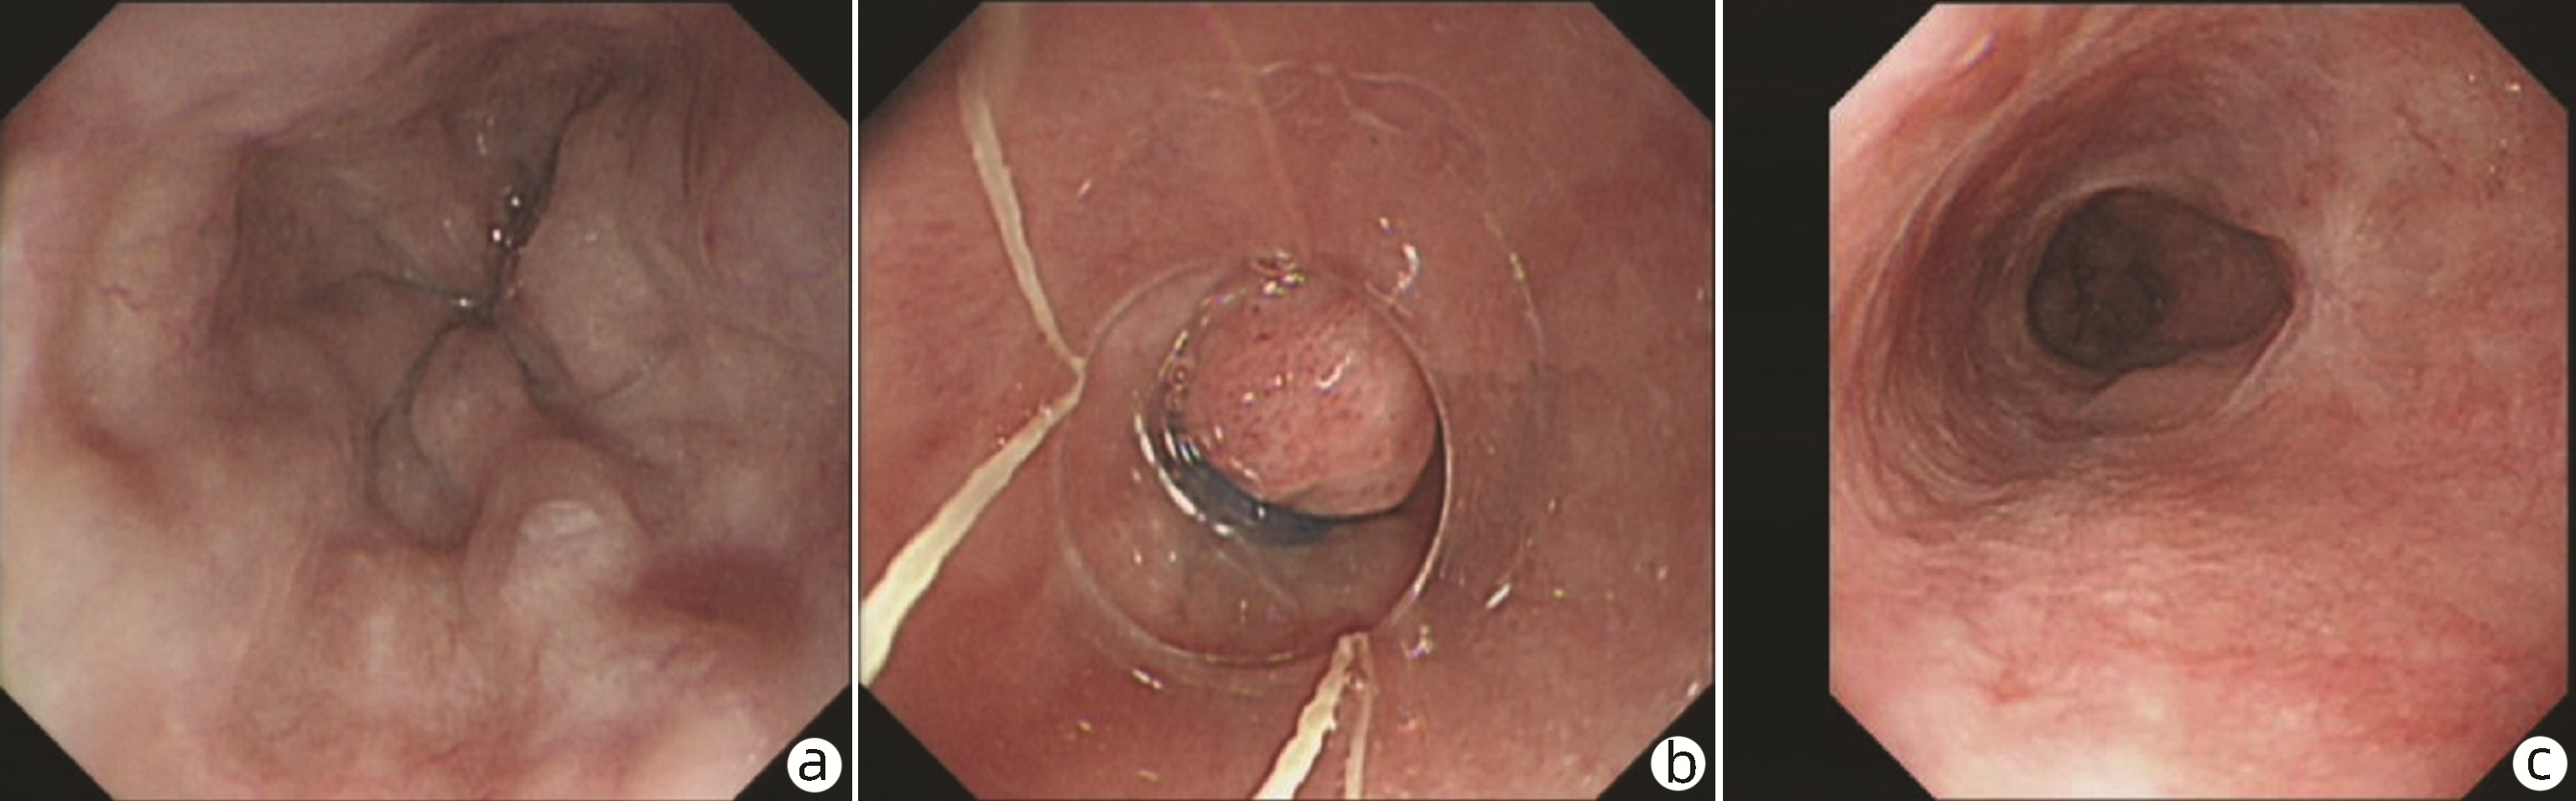

Endoscopic sequential ligation for treatment of esophageal and gastric varices with duodenal varices: A case report

Hao WEN, Zhaohui HE, Tong JIANG, Guoqing SHI

2023, 39(3): 637-639. DOI: 10.3969/j.issn.1001-5256.2023.03.024

Abstract(880) HTML (273) PDF (2676KB)(104)

Abstract: